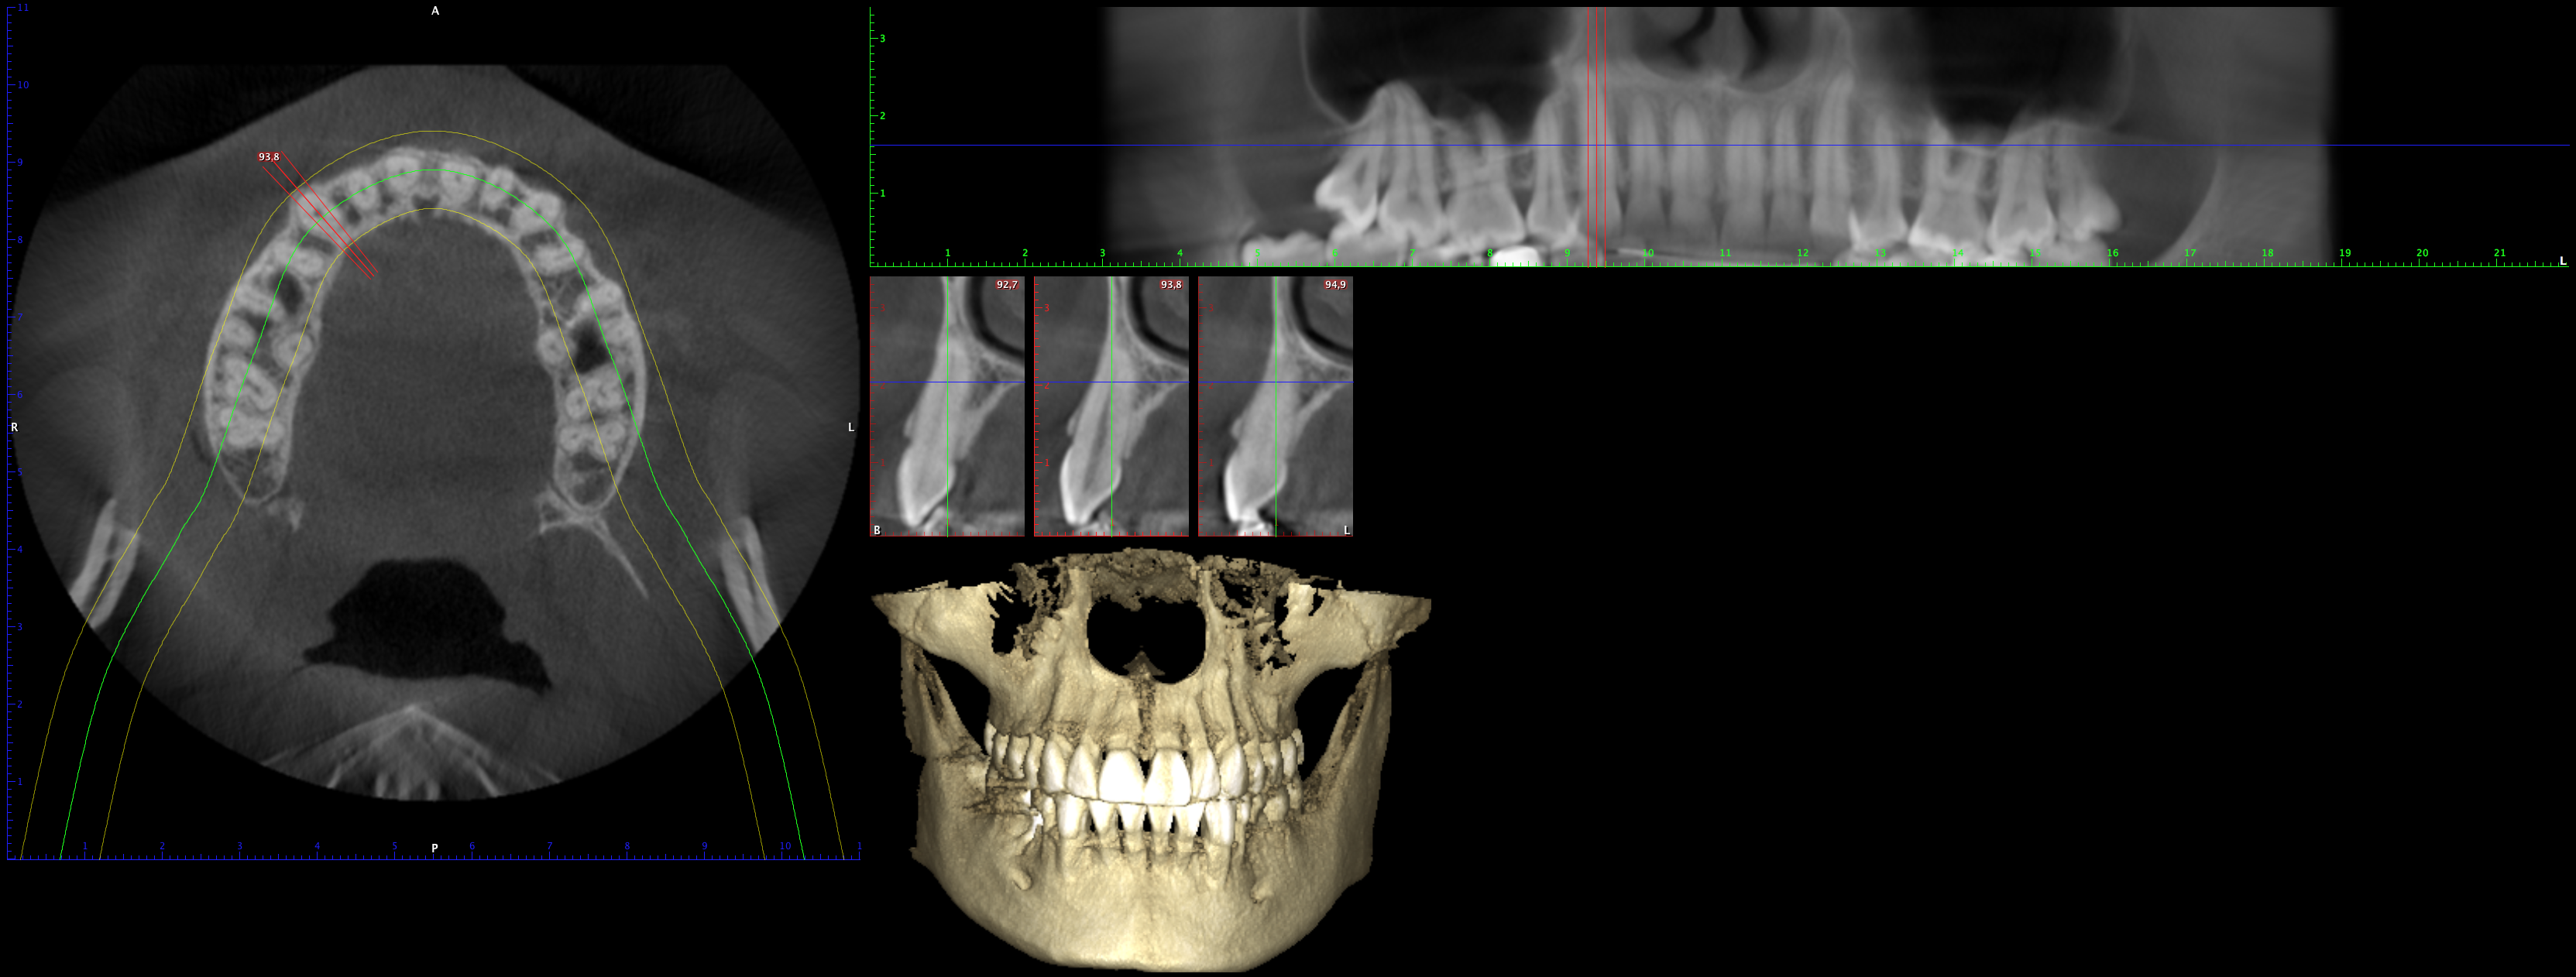

En PROTAC conseguimos una combinación ideal de calidad de imagen y usabilidad de alto nivel, ya que disponemos de una unidad CBCT(Cone Beam Computed Tomography) de última generación que supone un extraordinario avance en la evolución del procesamiento de imágenes de haz cónico, obteniendo una calidad de imagen optimizada, reduciendo los artefactos y garantizando imágenes de mayor contraste, para conseguir así satisfacer las necesidades del exigente procesamiento de imágenes maxilofaciales en todos los entornos clínicos. Nuestro innovador software Planmeca Romexis® ofrece herramientas especialmente diseñadas para especialistas en implantología, endodoncia, periodoncia, prostodoncia, ortodoncia, cirugía maxilofacial y otorrinolaringología.

Nuestra unidad de escáner y radiografía dental y nuestro software de procesamiento de imágenes brinda una combinación innovadora de imágenes 2D y 3D que le ofrecen una visión más completa para conocer con mayor exactitud las necesidades de sus pacientes.

Unidad CBCT de última generación con una calidad de imagen optimizada.

Software con herramientas especializadas para implantología, endodoncia, periodoncia, prostodoncia, ortodoncia, cirugía maxilofacial y otorrinolaringología.

Imágenes 2D y 3D más completas para conocer con mayor exactitud las necesidades de sus pacientes.